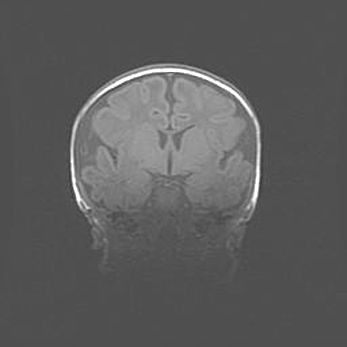

Церебральная ишемия II.

Возраст: 5 дней

Вес: 3400 г

Пол: женский

Окружность головы: 35 см

Срок гестации: 39 недель

Церебральная ишемия – это заболевание, характеризующееся недостаточностью (гипоксией) либо полным прекращением (аноксией) снабжения мозга кислородом по причине закупорки одного или нескольких сосудов. Это приводит к  что метаболическим расстройствам различной степени тяжести в тканях головного мозга, развитию коагуляционных некрозов и гибели нейронов.